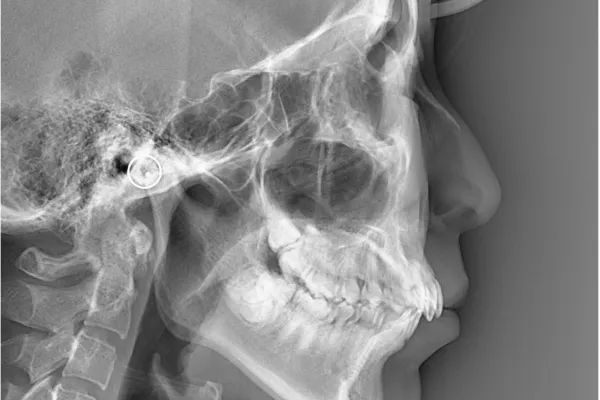

セファロレントゲン

矯正専用のレントゲン装置で、顔の骨格を調べることが可能です。矯正方針を策定するために役立ちます。